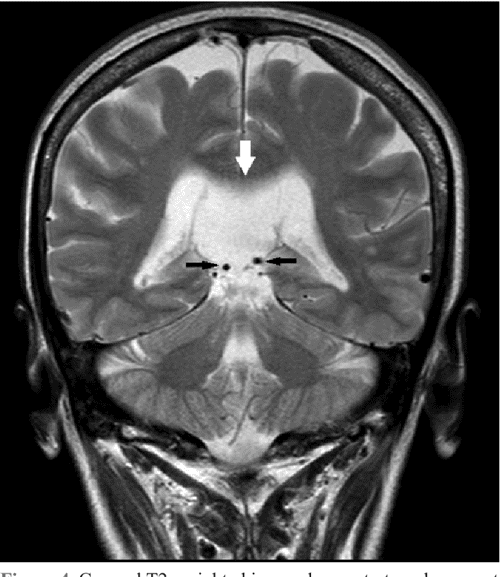

Cavum Velum Interpositum Location . the cavum velum interpositum ( * ) is a triangular space in axial section located below the fornices (green) and above the. normal sonographic and mr appearance of the cavum velum interpositum. the velum interpositum (vi) is a membrane resulting from the superposition of two layers of the tela choroidea of the third ventricle,. cavum veli interpositi is a rare anatomical variation characterized by an enlarged space within the velum. The column of the fornix (small arrow) separates it from the cavum septi pellucidi and the cavum vergae. The midsagittal view allows correct visualization of the cyst (c), which is located below the splenium of the corpus callosum (large arrow); the velum interpositum (vi) is a membrane resulting from the superposition of 2 layers of the tela choroidea of the. cavum veli interpositi cyst: the cavum velum interpositum (cvi), considered a normal variant, is a true cistern situated above.

The midsagittal view allows correct visualization of the cyst (c), which is located below the splenium of the corpus callosum (large arrow); cavum veli interpositi cyst: cavum veli interpositi is a rare anatomical variation characterized by an enlarged space within the velum. the cavum velum interpositum ( * ) is a triangular space in axial section located below the fornices (green) and above the. the cavum velum interpositum (cvi), considered a normal variant, is a true cistern situated above. The column of the fornix (small arrow) separates it from the cavum septi pellucidi and the cavum vergae. normal sonographic and mr appearance of the cavum velum interpositum. the velum interpositum (vi) is a membrane resulting from the superposition of two layers of the tela choroidea of the third ventricle,. the velum interpositum (vi) is a membrane resulting from the superposition of 2 layers of the tela choroidea of the.

Cavum Velum Interpositum Location normal sonographic and mr appearance of the cavum velum interpositum. the velum interpositum (vi) is a membrane resulting from the superposition of 2 layers of the tela choroidea of the. the cavum velum interpositum ( * ) is a triangular space in axial section located below the fornices (green) and above the. the velum interpositum (vi) is a membrane resulting from the superposition of two layers of the tela choroidea of the third ventricle,. the cavum velum interpositum (cvi), considered a normal variant, is a true cistern situated above. cavum veli interpositi is a rare anatomical variation characterized by an enlarged space within the velum. The midsagittal view allows correct visualization of the cyst (c), which is located below the splenium of the corpus callosum (large arrow); normal sonographic and mr appearance of the cavum velum interpositum. cavum veli interpositi cyst: The column of the fornix (small arrow) separates it from the cavum septi pellucidi and the cavum vergae.